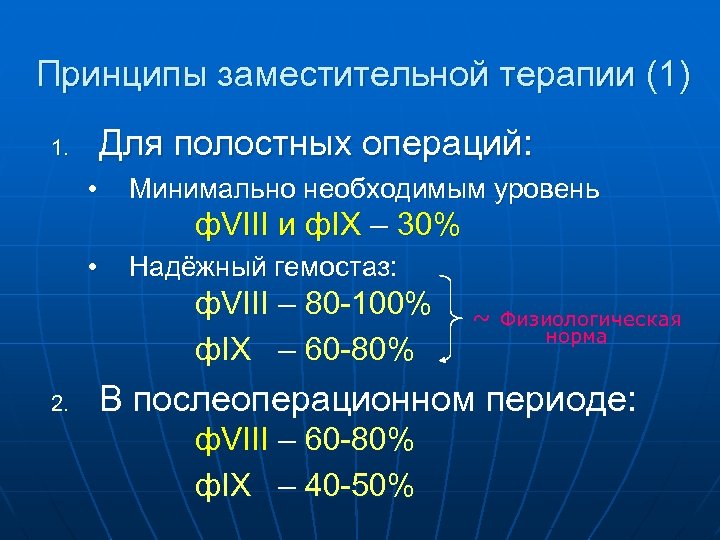

Принципы заместительной терапии (1) Для полостных операций: 1. • Минимально необходимым уровень ф. VIII и ф. IX – 30% • Надёжный гемостаз: ф. VIII – 80 -100% ф. IX – 60 -80% 2. ~ Физиологическая норма В послеоперационном периоде: ф. VIII – 60 -80% ф. IX – 40 -50%